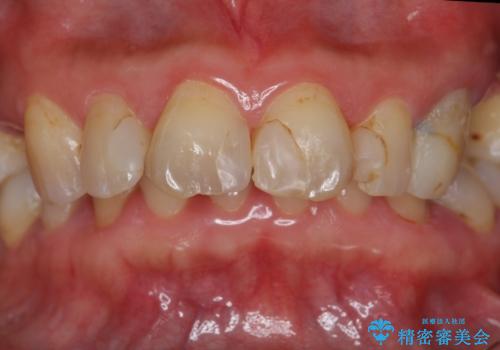

- 矯正治療後に、前歯の樹脂の詰め物のやりかえを提案していましたが、治療は当時行いませんでした。

その後3年間来院がなく、その間に前歯の虫歯の進行があり、治療を行いました。

やはり、樹脂で虫食い状になってしまうと虫歯が進行しやすくなっているためクラウンがおすすめです。

下の前歯との距離(クリアランス)が大きくは取れなかったため、ジルコニアクラウンではなくe-maxクラウンにしました。

また、歯ぎしりでセラミックがかけるのを防ぐために、就寝時にはナイトガードを装着してもらっています。